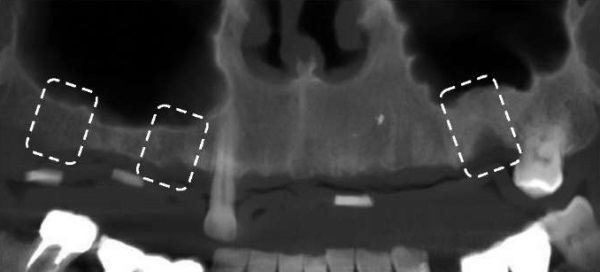

По данным конусно-лучевой компьютерной томографии, на верхней челюсти визуализируется частичное отсутствие зубов, отмечается атрофия кости альвеолярного отростка верхней челюсти. Верхнечелюстные пазухи умеренно пневматизированы, без патологических изменений. Объем кости достаточен для установки дентальных имплантатов (рис. 4).

Рис. 4. Снимок конусно-лучевой компьютерной томографии пациента А. Отмечается атрофия кости альвеолярного отростка верхней челюсти (отмечено фигурами)

Примечание: фотография выполнена авторами.

Fig. 4. Cone beam computed tomography image of patient A. The atrophy of maxillary alveolar process is noted (marked with rectangles)

Note: The photograph was taken by the authors.